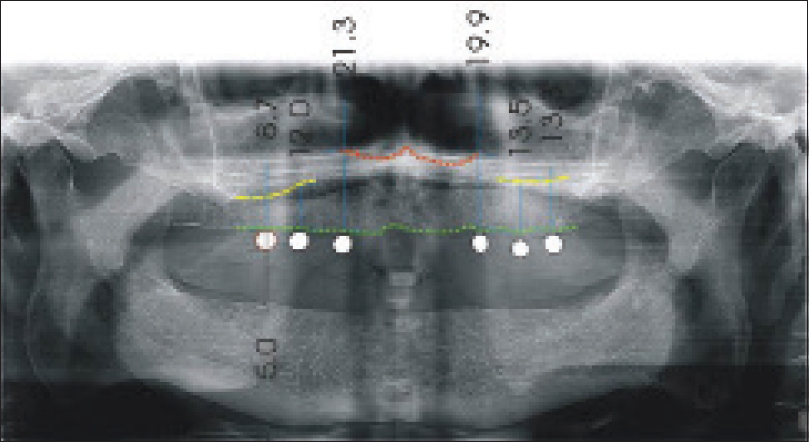

4. Using the panoramic images provide more and detailed coverage for periodontal bone defects, periapical lesions, and pathological jaw lesions than bitewings, thus extending the diagnostic benefit of pan bitewings as compared to intraoral bitewings.

5. The Less X-ray panoramic is radiation exposure. A panoramic bitewing study may cut radiation dose by 40% in comparison with intraoral, bitewing X-ray studies.